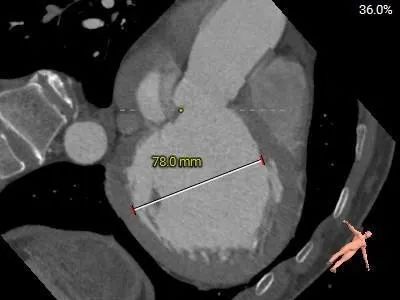

心室

左心室扩大

患者男性,因“间断气短5月余,再发10余天”入院,10余天前再发气短不适,活动耐量差。查心脏超声提示:左室(前后径、左右径、长径)83、76、92mm,室间隔:厚度9mm,左心功能:EF:22%。收缩期主动脉瓣前向血流速度正常,Vmax:164cm/s;舒张期期下可见大量反流面积约10.4cm²,容积约18ml。

• 左心室扩大,术中密切关注血流动力学变化,备体外循环或ECMO。